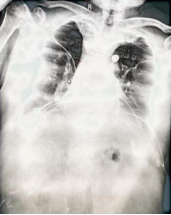

2025/11/16: 床旁胸片

急诊胸部正位片: 1.双肺透过度减低,纹理模糊,散在索条,请结合CT 2.心影饱满,结合临床相关检查3.双侧胸腔积液4.双侧多发肋骨走行欠规整